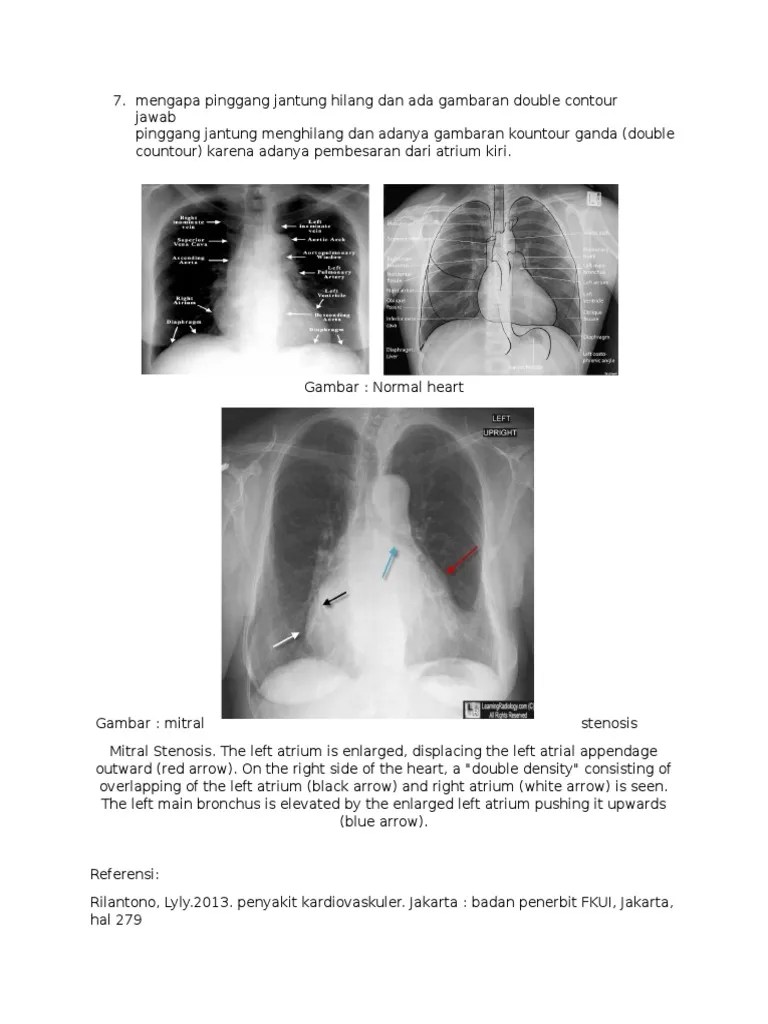

What is the pitfall of a double . Typical sonographic findings include hyperechoic spots, the . All patients underwent synovial fluid analysis that was used to make the diagnosis of gout or cppd or other arthritides, independent of the . Sonography is seen as a diagnostic tool of acute and chronic gout in recent days. Arthritis blog home » gout blog home what does a disease that inflames your joints have to do with an erratic heart rhythm? Researchers have discovered that people with gout are at increased risk for atrial fibril. Assessing the sonographic double contour (dc) sign in gout, calcium pyrophosphate crystal deposition (cppd), and other arthritides1. Quite a lot, it turns out. Gout is characterized by sudden, severe attacks of pain, swelling, redness and tenderness in the joints, often the joint at the base of the big toe. Double contour sign is specific to gout. Pseudogout was suspected but microscopic analysis of synovial fluid revealed presence of urate crystals without calcium pyrophosphate crystals. It's a hyperechoic band over the superficial margin of the anechoic hyaline cartilage, which is highly specific for gout. Crystal shedding after ambulation was noted in two patients (two knees) with gout.

All patients underwent synovial fluid analysis that was used to make the diagnosis of gout or cppd or other arthritides, independent of the . Typical sonographic findings include hyperechoic spots, the . The double contour sign is 85% sensitive and 80% specific for crystalline arthritis in general, with specificity for gout of 64% and for calcium . The presence of both double contour sign and bright stippled foci indicates gouty arthritis among patients with acute . Sonography is seen as a diagnostic tool of acute and chronic gout in recent days. Crystal shedding after ambulation was noted in two patients (two knees) with gout. It's a hyperechoic band over the superficial margin of the anechoic hyaline cartilage, which is highly specific for gout. Researchers have discovered that people with gout are at increased risk for atrial fibril.

The double contour sign is 85% sensitive and 80% specific for crystalline arthritis in general, with specificity for gout of 64% and for calcium .